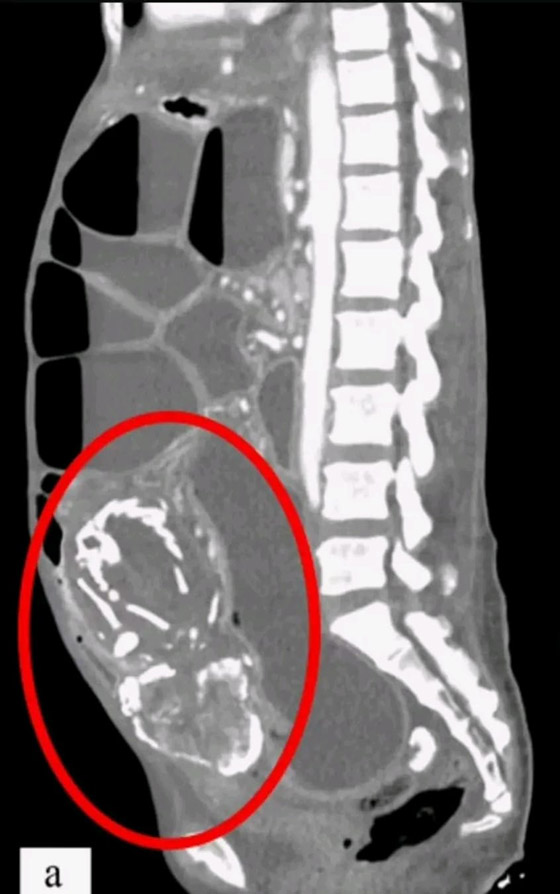

"اللي يعيش ياما يشوف".. ينطبق هذا المثل على واقعة شهدتها المكسيك وبطلتها كانت امرأة ثمانينية! فقد أدهشت السيدة-التي تبلغ من العمر 84 عاما من دورانجو بالمكسيك- المسعفين عندما اكتشفوا أن آلام البطن التي تشكو منها لم تكن إلا جنينا محنطا في رحمها منذ ما يزيد عن 4 عقود.

وبحسب ما ورد في صحيفة بريطانية، فإن المرأة ذهبت إلى عيادة الصحة العامة بسبب آلام مبرحة في بطنها، وبالفحص وجدوا أنها تحمل جنينا لم يكتب له أن يولد منذ 40 عاما. ويعتقد الأطباء أن الجنين قد تكلس، في حدث نادر للغاية يسمى "الجنين المتحجر أو المتكلس".

وعادة تنشأ الظروف المفجعة لهذه الحالة النادرة عندما يموت الجنين أثناء الحمل في البطن، ويكون كبيرا جدا بحيث لا يمكن للجسم امتصاصه، فيتكلس من الخارج كجزء من تفاعل جسم غريب، مما يحمي جسم الأم من الأنسجة الميتة للجنين ويقيها من العدوى.

ويعتقد المسعفون أن الطفل مات وتحنط في الأسبوع الأربعين من الحمل، بعد أن توقف عن النمو بشكل طبيعي. وأضافت التقارير أنه من غير المرجح أن تكون الأم قد تلقت الرعاية المناسبة في أثناء الحمل قبل حوالي 40 عاما.